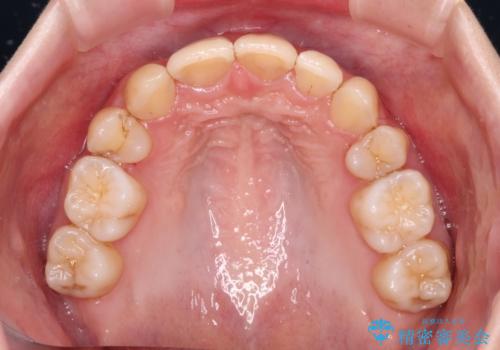

出っ歯を治したい ワイヤー装置による抜歯矯正

変則的な歯列であったため、奥歯がしっかりと咬み合うのか、前歯はしっかりと排列できるのかと不安ではありましたが、結果としてはきれいに整った歯列にて終了することができました。

口元を積極的に引っ込めるために、上下左右の小臼歯を4本抜歯することとしました。

右上前から2番目の歯が欠損しているため、①矯正治療により欠損部にスペースを作りインプラント補綴を行って前歯を左右対称に揃える、②左右非対称となるが、欠損補綴を行わずに排列する、のいずれかとなりますが、患者様と相談の上②にて矯正治療を行うこととしました。